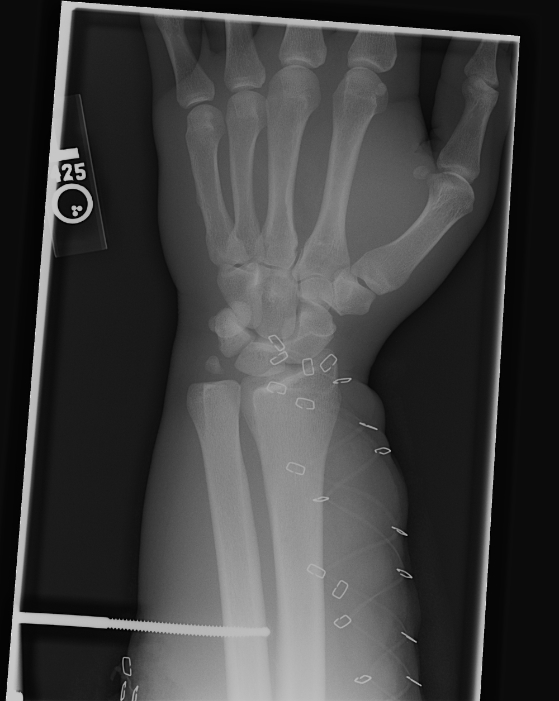

Nov 23, 2007 Here you can see the broken bones in his wrist. |